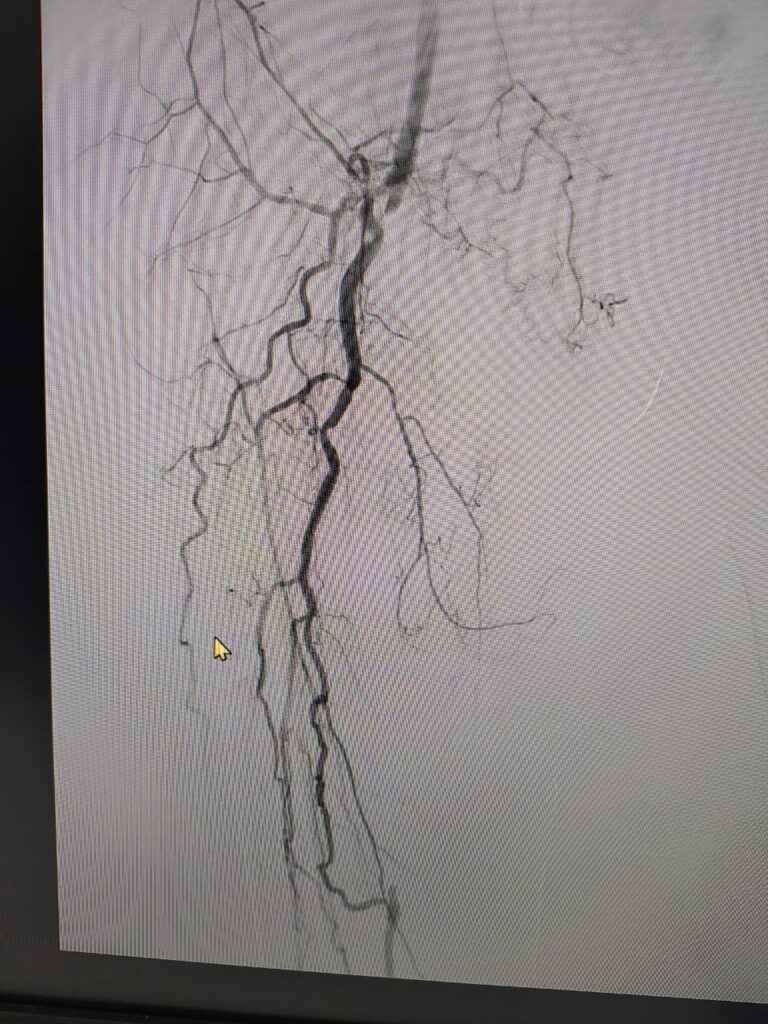

Case 3

A Minimally invasive procedure to open the blocked blood vessels in the lower limbs by Angioplasty